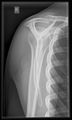

تصوير الكتف

أشعة إكس